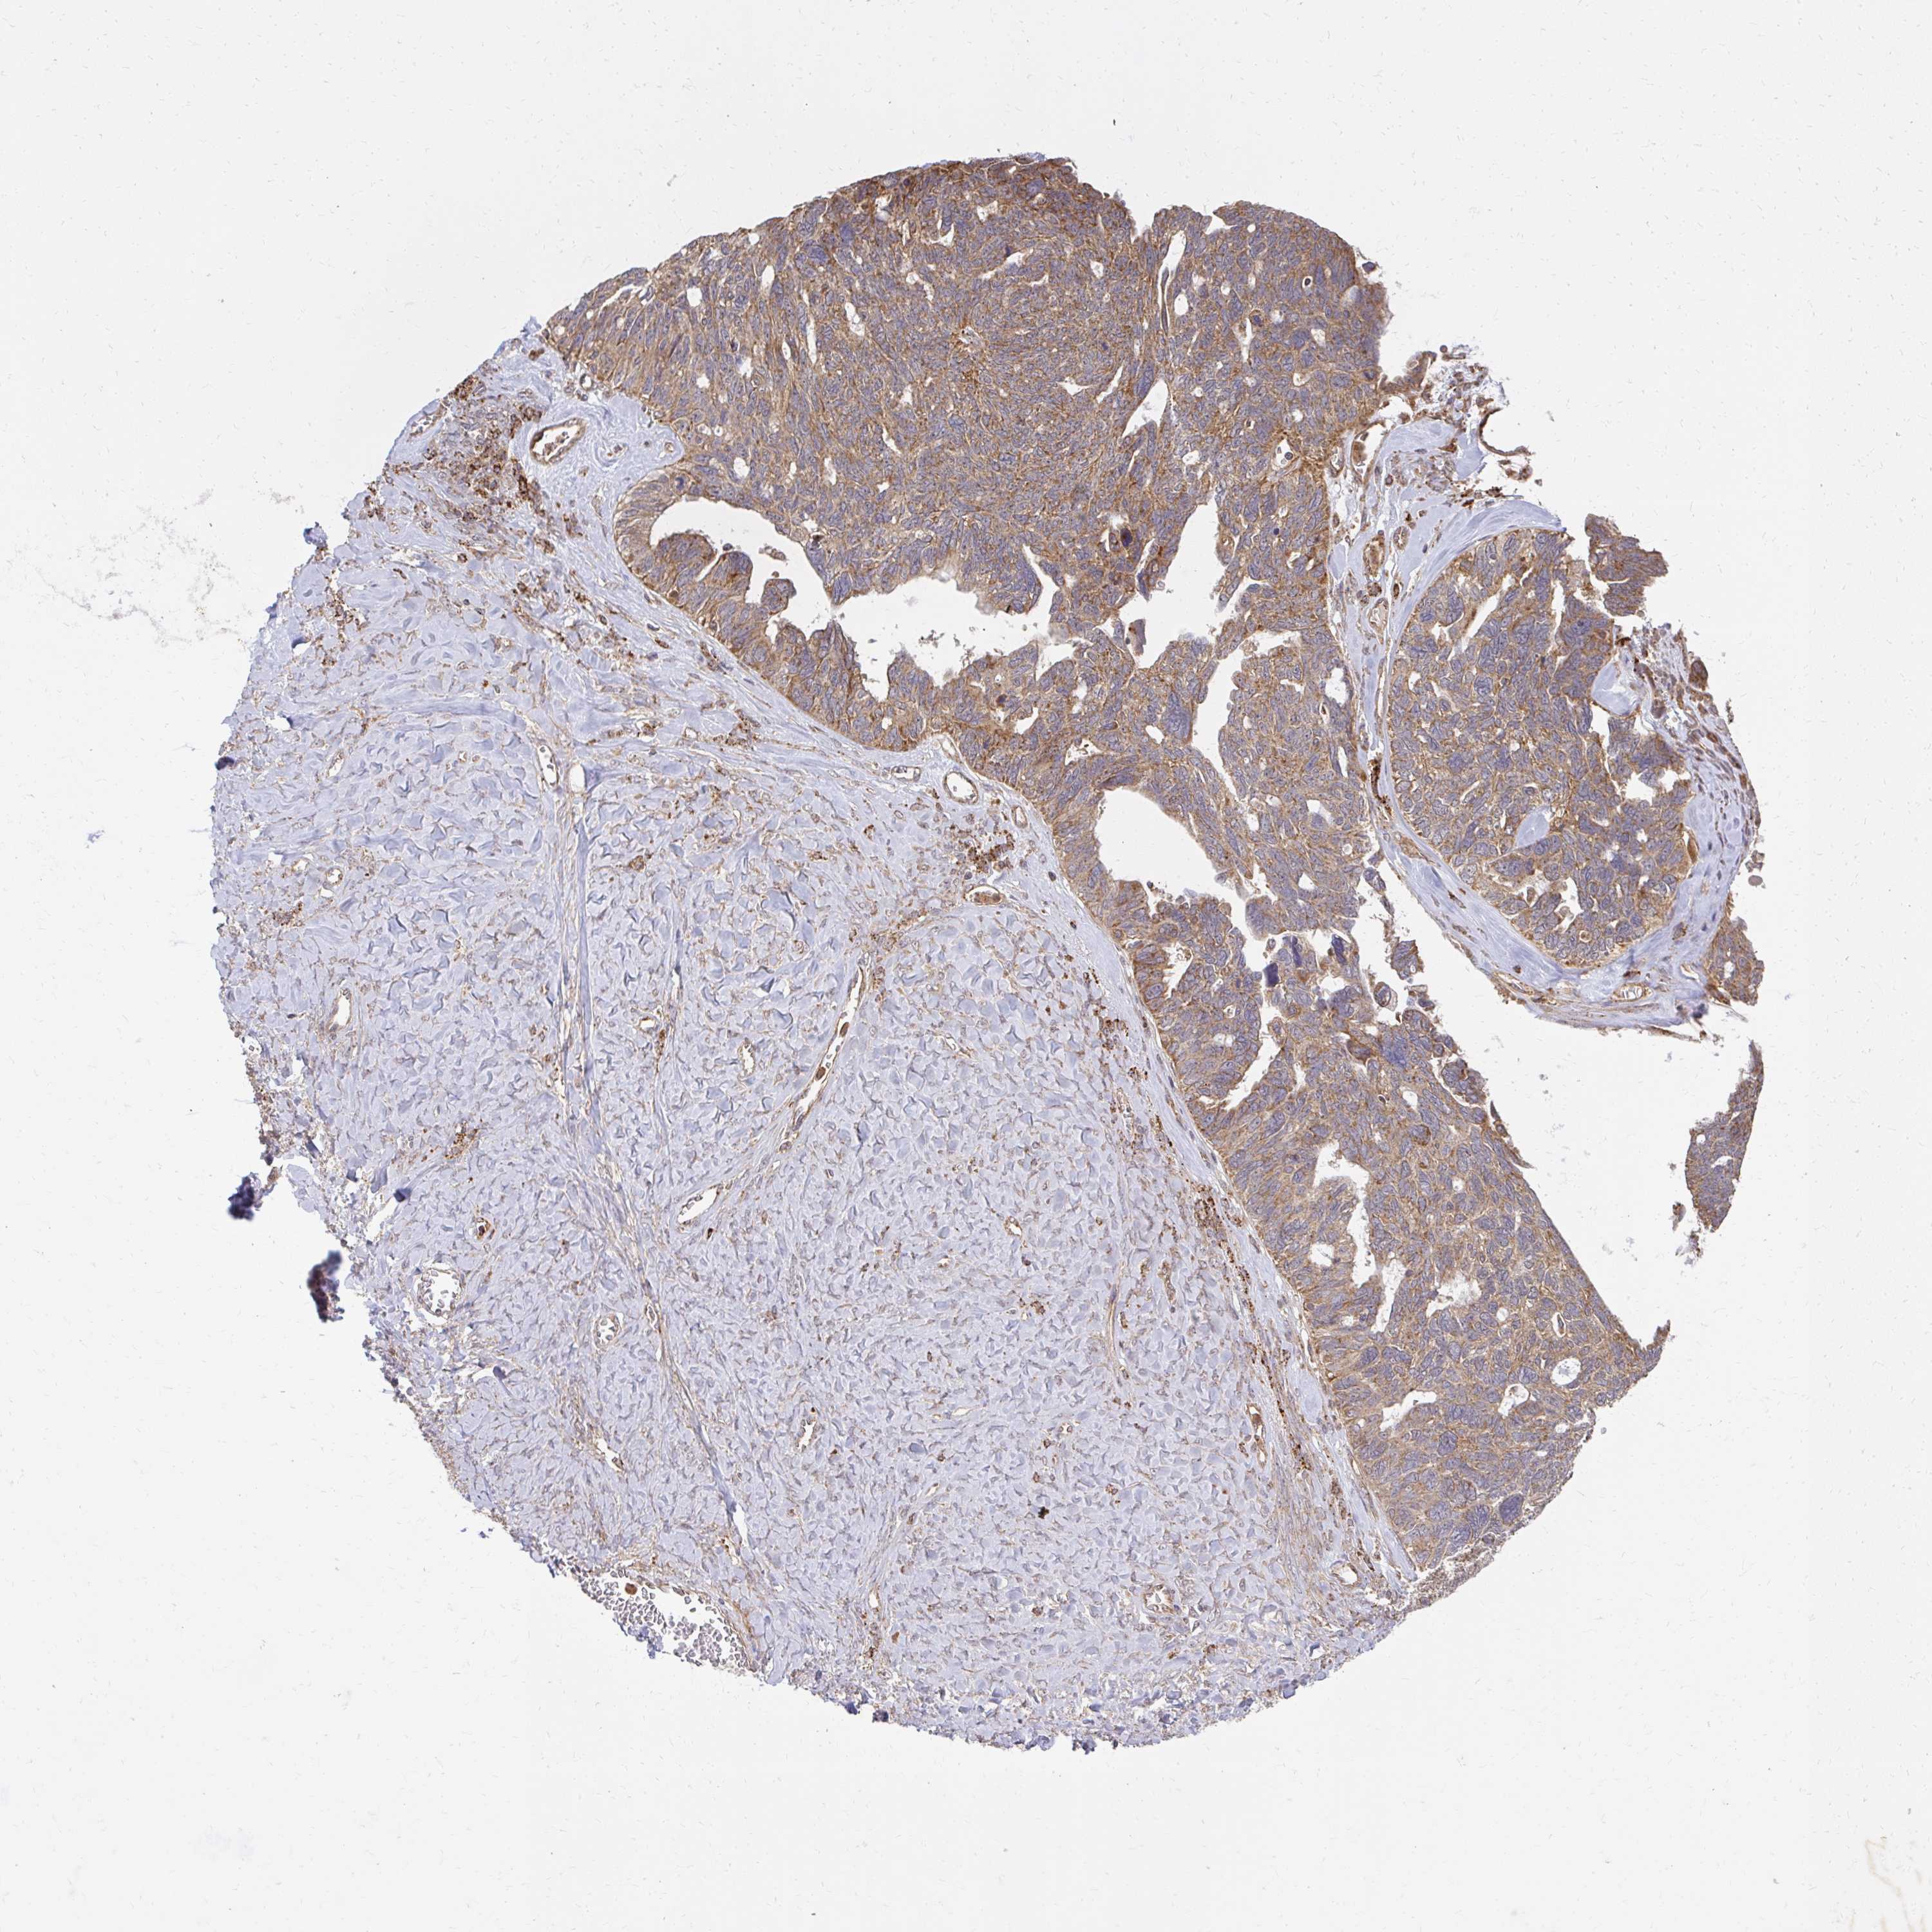

OVARIAN CANCER - Protein expressioni

A mouse-over function shows sample information and annotation data. Click on an image to view it in a full screen mode. Samples can be filtered based on level of antibody staining by selecting one or several of the following categories: high, medium, low and not detected. The assay and annotation is described here.

Note that samples used for immunohistochemistry by the Human Protein Atlas do not correspond to samples in the TCGA dataset.

Antibody stainingi

Antibody staining in the annotated cell types in the current human tissue is reported as not detected, low, medium, or high, based on conventional immunohistochemistry profiling in selected tissues. This score is based on the combination of the staining intensity and fraction of stained cells.

Each image is clickable and will lead to virtual microscopy that enables deeper exploration of all samples and also displays staining intensity scores, fraction scores and subcellular localization as well as patient and tissue information for each sample.

Antibody HPA013695

Antibody HPA048508

Antibody CAB026011

Staining

High

Medium

Low

Not detected

Cystadenocarcinoma, serous, NOS

Carcinoma, endometroid

Cystadenocarcinoma, mucinous, NOS

Carcinoma, NOS